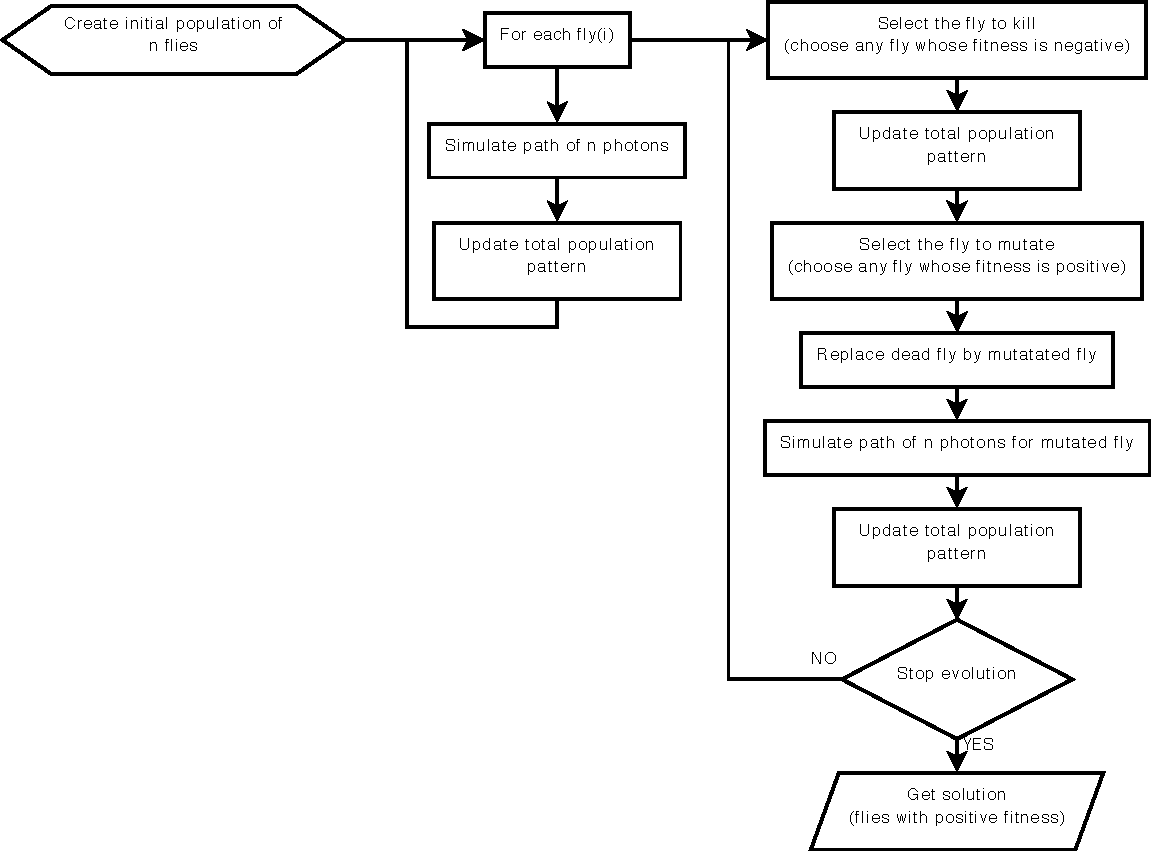

This work is based on a cooperative co-evolution algorithm called `Fly Algorithm', which is an evolutionary algorithm (EA) where individuals are called `flies'. It is a specific case of the `Parisian Approach' where the solution of an optimisation problem is a set of individuals (e.g. the whole population) instead of a single individual (the best one) as in typical EAs. The optimisation problem considered here is tomography reconstruction in positron emission tomography (PET). It estimates the concentration of a radioactive substance (called a radiotracer) within the body. Tomography, in this context, is considered as a difficult ill-posed inverse problem. The Fly Algorithm aims at optimising the position of 3-D points that mimic the radiotracer. At the end of the optimisation process, the fly population is extracted as it corresponds to an estimate of the radioactive concentration. During the optimisation loop a lot of data is generated by the algorithm, such as image metrics, duration, and internal states. This data is recorded in a log file that can be post-processed and visualised. We propose using information visualisation and user interaction techniques to explore the algorithm's internal data. Our aim is to better understand what happens during the evolutionary loop. Using an example, we demonstrate that it is possible to interactively discover when an early termination could be triggered. It is implemented in a new stopping criterion. It is tested on two other examples on which it leads to a 60% reduction of the number of iterations without any loss of accuracy. Keywords: Fly Algorithm; Tomography reconstruction; Information visualisation; Data exploration; Artificial evolution; Parisian evolution. |

The Fly Algorithm was initially developed for 3-D robot vision applications. It consists in solving the inverse problem of shape reconstruction from projections by evolving a population of 3-D points in space (the `flies'), using an evolutionary optimisation strategy. Here, in its version dedicated to tomographic reconstruction in medical imaging, the flies are mimicking radioactive photon sources. Evolution is controlled using a fitness function based on the discrepancy of the projections simulated by the flies with the actual pattern received by the sensors. The reconstructed radioactive concentration is derived from the population of flies, i.e. a collection of points in the 3-D Euclidean space, after convergence. `Good' flies were previously binned into voxels. In this paper, we study which flies to include in the final solution and how this information can be sampled to provide more accurate datasets in a reduced computation time. We investigate the use of density fields, based on Metaballs and on Gaussian functions respectively, to obtain a realistic output. The spread of each Gaussian kernel is modulated in function of the corresponding fly fitness. The resulting volumes are compared with previous work in terms of normalised-cross correlation. In our test-cases, data fidelity increases by more than 10% when density fields are used instead of binning. Our method also provides reconstructions comparable to those obtained using well-established techniques used in medicine (filtered back- projection and ordered subset expectation-maximisation). Keywords: Fly algorithm; Evolutionary computation; tomography reconstruction; iterative algorithms; inverse problems; co-operative co-evolution |

Our work is based on a Cooperative Co-evolution Algorithm -- the Fly algorithm -- in which individuals correspond to 3-D points. The Fly algorithm uses two levels of fitness function: i) a local fitness computed to evaluate a given individual (usually during the selection process) and ii) a global fitness to assess the performance of the population as a whole. This global fitness is the metrics that is minimised (or maximised depending on the problem) by the optimiser. Here the solution of the optimisation problem corresponds to a set of individuals instead of a single individual (the best individual) as in classical evolutionary algorithms. The Fly algorithm heavily relies on mutation operators and a new blood operator to insure diversity in the population. To lead to accurate results, a large mutation variance is often initially used to avoid local minima (or maxima). It is then progressively reduced to refine the results. Another approach is the use of adaptive operators. However, very little research on adaptive operators in Fly algorithm has been conducted. We address this deficiency and propose 4 different fully adaptive mutation operators in the Fly algorithm: positrons, and the final solution of the algorithm approximates the radioactivity concentration. The view and analysis four mutation operators, which are Basic Mutation, Adaptive Mutation Variance, Dual Mutation, and Directed Mutation. Due to the complex nature of the search space, (kN-dimensions, with k the number of genes per individuals and N the number of individuals in the population), we favour operators with a low maintenance cost in terms of computations. Their impact on the algorithm efficiency is analysed and validated on positron emission tomography (PET) reconstruction. Keywords: evolutionary algorithms, Parisian approach, reconstruction algorithms, positron emission tomography, mutation operator |

Our work is based on a Cooperative Co-evolution Algorithm -- the Fly algorithm -- in which individuals correspond to 3-D points. The Fly algorithm uses two levels of fitness function: i) a local fitness computed to evaluate a given individual (usually during the selection process) and ii) a global fitness to assess the performance of the population as a whole. This global fitness is the metrics that is minimised (or maximised depending on the problem) by the optimiser. Here the solution of the optimisation problem corresponds to a set of individuals instead of a single individual (the best individual) as in classical evolutionary algorithms. The Fly algorithm heavily relies on mutation operators and a new blood operator to insure diversity in the population. To lead to accurate results, a large mutation variance is often initially used to avoid local minima (or maxima). It is then progressively reduced to refine the results. Another approach is the use of adaptive operators. However, very little research on adaptive operators in Fly algorithm has been conducted. We address this deficiency and propose 4 different fully adaptive mutation operators in the Fly algorithm: positrons, and the final solution of the algorithm approximates the radioactivity concentration. The view and analysis four mutation operators, which are Basic Mutation, Adaptive Mutation Variance, Dual Mutation, and Directed Mutation. Due to the complex nature of the search space, (kN-dimensions, with k the number of genes per individuals and N the number of individuals in the population), we favour operators with a low maintenance cost in terms of computations. Their impact on the algorithm efficiency is analysed and validated on positron emission tomography (PET) reconstruction. Keywords: evolutionary algorithms, Parisian approach, reconstruction algorithms, positron emission tomography, mutation operator |

This paper shows new resutls of our artificial evolution algorithm for Positron Emission Tomography (PET) reconstruction. This imaging technique produces datasets corresponding to the concentration of positron emitters within the patient. Fully three-dimensional (3D) tomographic reconstruction requires high computing power and leads to many challenges. Our aim is to produce high quality datasets in a time that is clinically acceptable. Our method is based on a co-evolution strategy called the “Fly algorithm”. Each fly represents a point in space and mimics a positron emitter. Each fly position is progressively optimised using evolutionary computing to closely match the data measured by the imaging system. The performance of each fly is assessed based on its positive or negative contribution to the performance of the whole population. The final population of flies approximates the radioactivity concentration. This approach has shown promising results on numerical phantom models. The size of objects and their relative concentrations can be calculated in two-dimensional (2D) space. In (3D), complex shapes can be reconstructed. In this paper, we demonstrate the ability of the algorithm to fidely reconstruct more anatomically realistic volumes. Keywords: Evolutionary computation, inverse problems, adaptive algorithm, Nuclear medicine, Positron emission tomography, Reconstruction algorithms |

We present and analyse the behaviour of specialised operators designed for cooperative coevolution strategy in the framework of 3D tomographic PET reconstruction. The basis is a simple cooperative co-evolution scheme (the “fly algorithm”), which embeds the searched solution in the whole population, letting each individual be only a part of the solution. An individual, or fly, is a 3D point that emits positrons. Using a cooperative co-evolution scheme to optimize the position of positrons, the population of flies evolves so that the data estimated from flies matches measured data. The final population approximates the radioactivity concentration. In this paper, three operators are proposed, threshold selection, mitosis and dual mutation, and their impact on the algorithm efficiency is experimentally analysed on a controlled test-case. Their extension to other cooperative co-evolution schemes is discussed. |

This paper presents an evolutionary approach for image reconstruction in positron emission tomography (PET). Our reconstruction method is based on a cooperative coevolution strategy (also called Parisian evolution): the “fly algorithm”. Each fly is a 3D point that mimics a positron emitter. The flies' position is progressively optimised using evolutionary computing to closely match the data measured by the imaging system. The performance of each fly is assessed using a “marginal evaluation” based on the positive or negative contribution of this fly to the performance of the population. Using this property, we propose a “thresholded-selection” method to replace the classical tournament method. A mitosis operator is also proposed. It is triggered to automatically increase the population size when the number of flies with negative fitness becomes too low. |

This paper presents a method to take advantage of artificial evolution in positron emission tomography reconstruction. This imaging technique produces datasets that correspond to the concentration of positron emitters through the patient. Fully 3D tomographic reconstruction requires high computing power and leads to many challenges. Our aim is to reduce the computing cost and produce datasets while retaining the required quality. Our method is based on a coevolution strategy (also called Parisian evolution) named “Fly algorithm”. Each fly represents a point of the space and acts as a positron emitter. The final population of flies corresponds to the reconstructed data. Using “marginal evaluation”, the fly's fitness is the positive or negative contribution of this fly to the performance of the population. This is also used to skip the relatively costly step of selection and simplify the evolutionary algorithm. |

Purpose: We propose an evolutionary approach for image

the “fly algorithm”. |